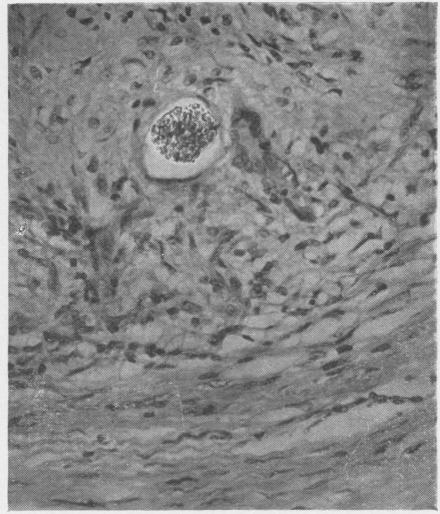

Beryllium granuloma of the skin.

Br J Ind Med. 1954 Jan;11(1):45-8. doi: 10.1136/oem.11.1.45.